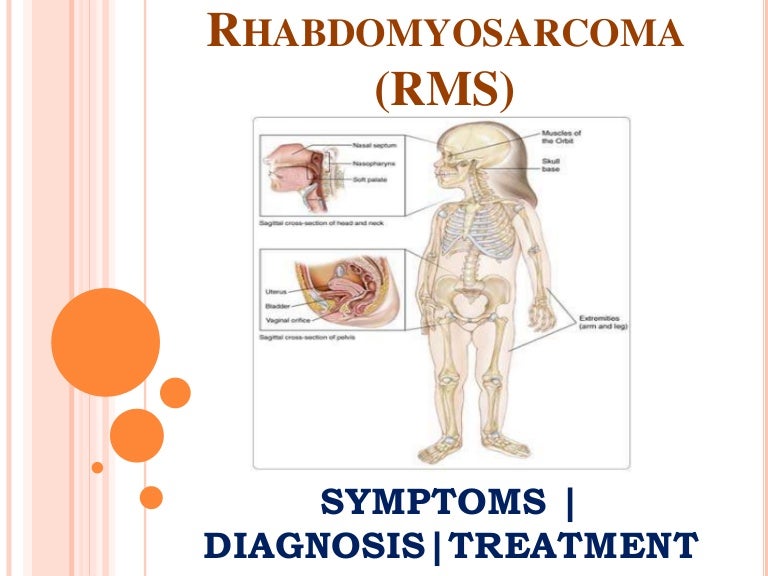

Rhabdomyosarcoma (RMS): Information On Symptoms, Diagnosis And Treatm…

pt.slideshare.net

pt.slideshare.net

PPT - Rhabdomyosarcoma (RMS): Information On Symptoms, Diagnosis And

www.slideserve.com

www.slideserve.com

rhabdomyosarcoma symptoms treatment rms diagnosis information ppt powerpoint presentation